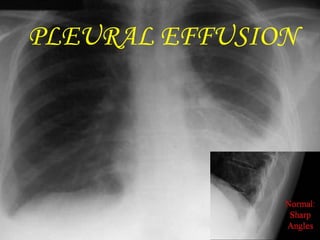

PLEURAL EFFUSION

Bilateral pleural effusions

• #29 Pleural effusion developing on the left